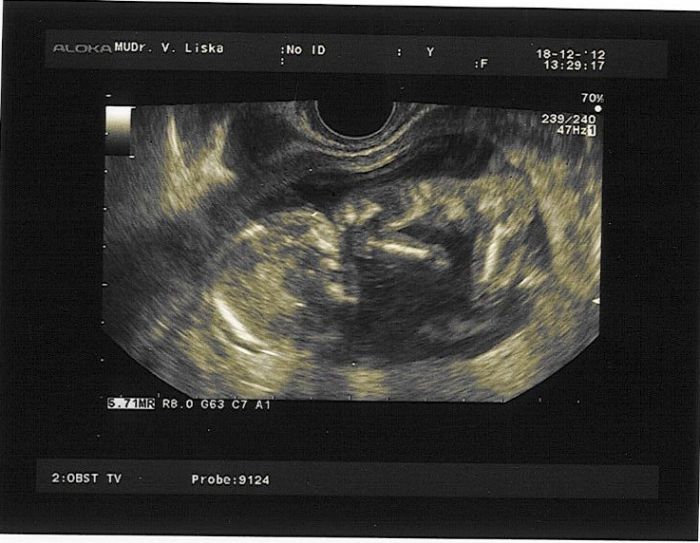

Já shodila v 1. trimestru 2 kg, zle mi bylo ale nezvracela jsem a zatím jsou pořád dole, i když břiško trošku roste, pořád se vejdu do původních kalhot, asi to je tím že jsem silnější.Včera jsem byla natočit si DVD a pro pár foteček pod stromeček.Jednu posílám už prcek začíná vypadat jak mimi.:-)

[251032] Včera to bylo 15+1 měří 9,2. Ja mam TP 10.6.2013, takže by si na tom měla být podobně.